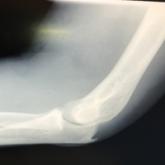

ArticleVascular Injury Following a Fall Onto an Outstretched HandAuthor:Jimmy Stickles, MDPublish date: July 5, 2017A 46-year-old man presented for evaluation of an injury to his left elbow after a fall.Read More